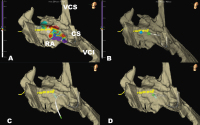

Abbildung 3: 3D-Anatomie (EnSiteX™) des rechten Vorhofes (RA) mit Sinus coronarius (CS), Vena cava superior (VCS) und Vena cava inferior (VCI). Die gelben Punkte kennzeichnen die His-Region. Der Kryo-Tip-Ablationskatheter (Freezor™ Xtra) ist mit grüner Spitze dargestellt. (A): Local Activation Time Map bei Stimulation aus dem rechten Ventrikel. Die früheste atriale Erregung ist in weiß, die späteste in violett dargestellt. (B): Markierung des erfolgreichen Kryo-Ablationspunktes (blau) direkt im His-Bereich. (C): Darstellung des Kryo-Ablationskatheters während der Kryo-Ablation ohne „Stabilize ABL“-Funktion. (D): Darstellung des Kryo-Ablationskatheters während der Kryo-Ablation mit „Stabilize ABL“-Funktion.